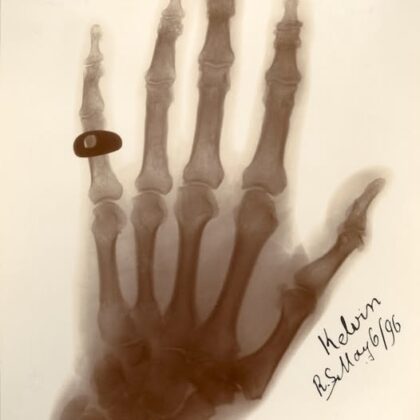

Ještě zbývá se vyjádřit k jednomu Kelvinovu výroku, jehož uvádění mě také dosti rozčiluje. Jde o výrok: „Rentgenové paprsky jsou jednoduše podvod.“ Ano, Lord Kelvin skutečně nejprve označoval objev rentgenových paprsků německým fyzikem Wilhelmem Röntgenem za podvod, či pohádku. Takže proč mám s tímto výrokem problém? Například proto, že se u něj někdy uvádí rok 1893. Ale Röntgen ohlásil svůj objev až koncem roku 1895. Kelvin se tedy v roce 1893 takto vyjádřit prostě nemohl. Pokud tedy nebyl jasnovidec, popřípadě cestovatel časem.

Navíc se tento výrok obvykle cituje zcela bez kontextu, který je přitom v tomto případě zcela zásadní. Ano, Kelvin opravdu nejdříve objevu nevěřil a byl k němu skeptický. Ale když říkáme A, musíme říci i B. Wilhelm Röntgen mu totiž poslal kopii svých poznámek. Kelvin si je podrobně přečetl a prohlédl si i Röntgenem přiložené fotografie.

To jej přesvědčilo natolik, aby napsal Röntgenovi dopis, v němž stálo: „Nemusím vám říkat, že když jsem si přečetl noviny, byl jsem velmi ohromen a potěšen. Nyní nemohu říct nic víc než vám vřele poblahopřát k velkému objevu, který jste učinil.“ A pozor! Tento dopis Kelvin odeslal již 17. ledna 1896, tedy jen několik týdnů po zveřejnění Röntgenova objevu!

A co více, později téhož roku si za pomoci nově objeveného rentgenového záření, označovaného v anglicky mluvícím světě jako paprsky X nechal nasnímat svou vlastní ruku. Takže bohužel, i zde se nám mýtus o slavném vědci, který zarputile odmítá nové objevy a není schopen přiznat chybu rozplývá jako pára nad hrncem.